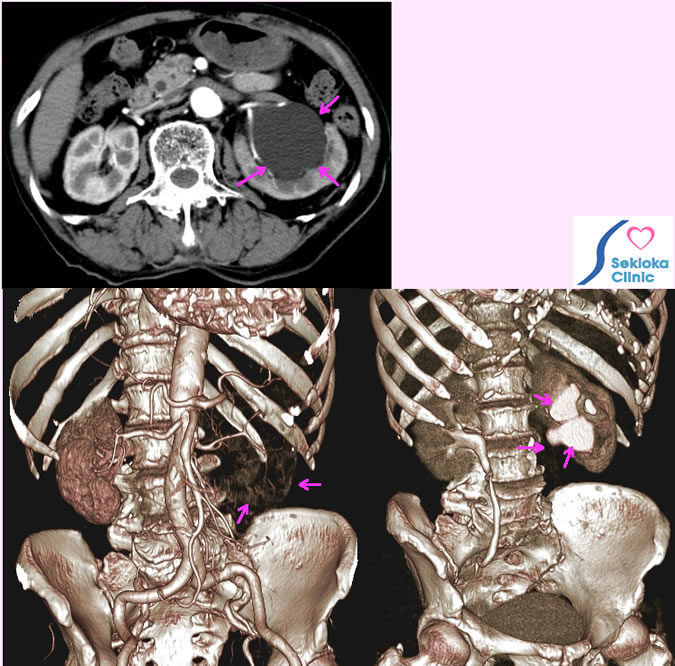

尿管がん

腰痛、すべり症で精査のためMDCTで撮影したところ偶然 左腎の腎盂拡張認める。

水腎症の原因精査のため造影MDCT施行、尿管閉塞を認めるが子宮・卵巣・膀胱に異常なく、尿管がん疑いにて 泌尿器科に紹介

治療

手術にて摘出